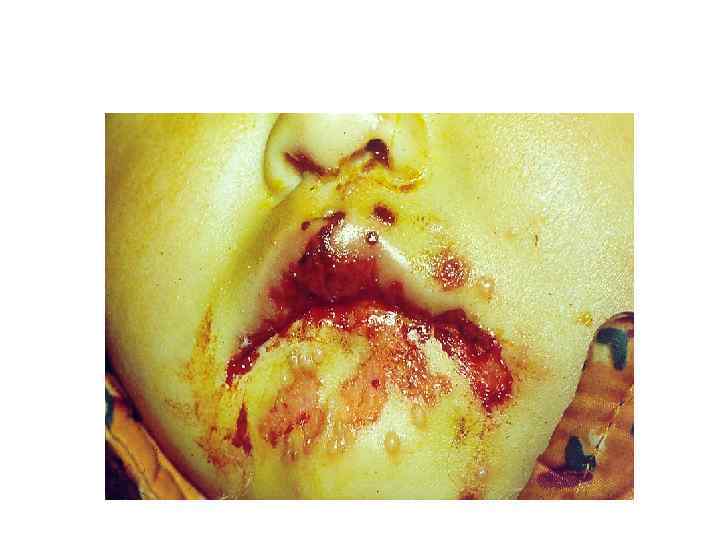

Осмотр: Внешний осмотр: Общий вид больного (habitus); Симметрия лица; Цвет кожных покровов лица, конечностей, открытых участков тела; • Состояние волосистой части головы; • Состояние красной каймы губ, конъюнктивы глаз, крыльев носа. • •

Осмотр собственно полости рта Общий осмотр слизистой оболочки: - цвет; - увлажненность; - наличие участков гиперемии; - наличие отека; - наличие элементов поражения (эрозии, язвы, налет и т. д. ); • - состояние выводных протоков слюнных желез. • • •